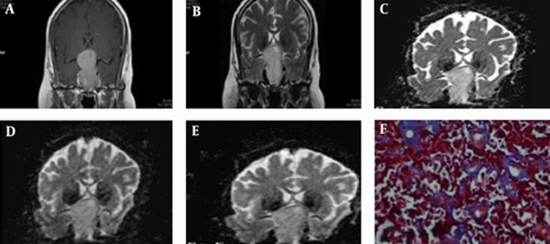

Is There Any Congruity Between Tumor Consistency in Pituitary Macroadenomas and Preoperative Diffusion Weighted Imaging and Apparent Diffusion Coefficient (ADC) Map?

Pituitary adenomas are the most common space-occupying lesions in the sellar region. Pituitary adenomas are usually soft, but 5 to 13% of macroadenomas are fibrous. The resection of firm tumors by curettage or suction is challenging. Therefore, preoperative knowledge of the pituitary adenomas consistency could help neurosurgeons plan more appropriate surgical procedures. In this regard, predicting fibrous adenomas by magnetic resonance imaging (MRI) is typically difficult and the results are controversial. We evaluated the correlation of pituitary adenoma consistency during tumor resection with preoperative diffusion-weighted images (DWI) findings and apparent diffusion coefficient (ADC) values.

45 consecutive patients (21 male, 24 female, mean age 43 ± 10) with pituitary macroadenoma were prospectively enrolled. Radiological evaluation with conventional MR and DWI images was done for all patients. Tumor consistency was evaluated at surgery and classified as soft, intermediated, and hard. Histological examination was performed on tumor specimens.

Based on the surgical findings, 12 (26.7%) tumors were classified as soft-, 30 (66.6%) as intermediate-, and 3 (6.7%) as hard-consistency macroadenomas. Although the collagen content showed an association with tumor consistency, neither tumor consistency nor collagen content and secretory status were correlated with conventional MRI measures and ADCs in different b values and planes.

Preoperative DW MRI was not useful to predict the tumor consistency, collagen content, and hormone-secreting status of pituitary macroadenomas.